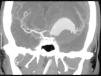

Mujer de 49 años. Ingresó en nuestra UCI remitida desde otro centro por coma secundario a hemorragia subaracnoidea. La angio-TAC craneal mostró la presencia de un aneurisma gigante fusiforme que englobaba la arteria cerebral media izquierda (ACM), con origen de difícil localización por el gran tamaño de la lesión (fig. 1). La ecografía cerebral realizada en la UCI (fig. 2) identificó un punto de entrada y salida de flujo sanguíneo en la trifurcación de la ACM izquierda (flechas). Sucesivos registros ecográficos cerebrales mostraron en cada latido el llenado de distal a proximal del saco aneurismático, y su posterior vaciamiento, confirmando su carácter disecante. Fue rechazado el tratamiento quirúrgico o endovascular hasta el control de la hipertensión intracraneal (PIC). Se practicó craniectomía descompresiva, y se mantuvo a la paciente en tratamiento médico, bajo sedo-relajación y con monitorización intraventricular de la PIC. En el décimo día presentó resangrado con hipertensión intracraneal refractaria y rápida evolución a muerte encefálica.